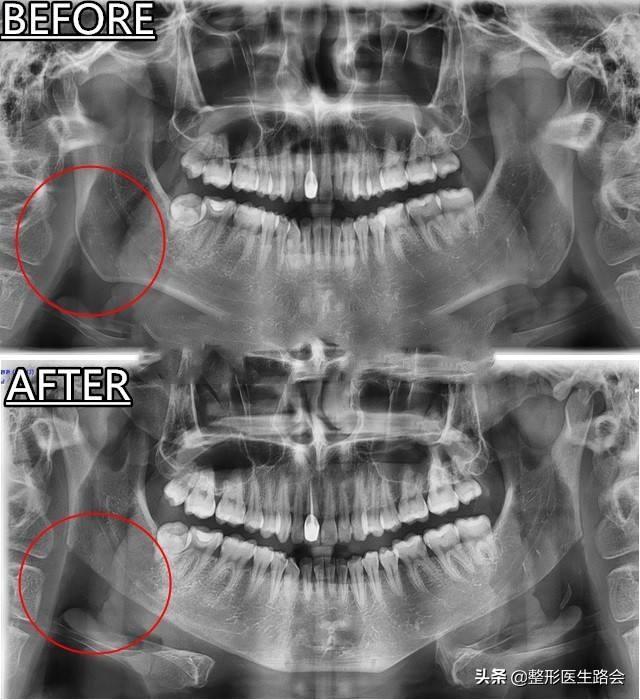

图片来自网络 仅供参考说明

下颌角切除